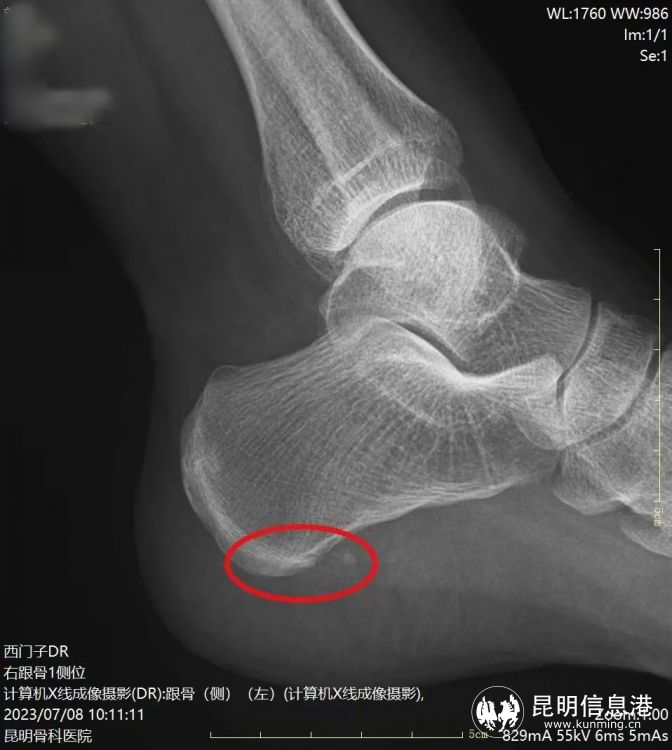

术后骨刺消失

“经检查发现刘女士不仅左足跟有跟骨骨刺,双足还有足底筋膜炎,本次微创手术只需在患者足内侧跟骨前结节处两侧各取一个0.2-0.5cm的小孔,建立镜下手术工作通道,就能在可视下磨除跟骨骨刺,筋膜松解,处理炎症组织。”昆明骨科医院手足显微外科主任李海波介绍说,这种新型的微创治疗手段对比起传统的治疗来讲有很大的优势,微创损伤小、恢复快、手术疼痛轻等特点,传统的跟痛症手术通常从跟骨内侧长斜形切口,长约5厘米,典型的“小手术、大切口”。